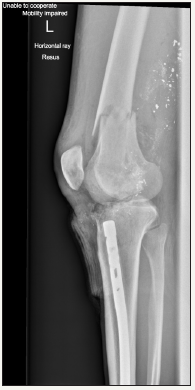

Figure 1: AP X-Ray of knee post-injury.

A 24 year old man presented to our hospital having accidentally shot himself in the left knee while cleaning a shotgun. He had sustained compound intra-articular distal femur and proximal tibia fractures with significant bone loss and moderate soft tissue injury (Figure 1 & 2). There was no associated neurovascular injury. He had an intramedullary tibial nail in situ from a previous tibial shaft fracture. This was an isolated injury and he was otherwise medically well. He underwent debridement, lavage, removal of the tibial nail and spanning external fixation in theatre. 48 hours later he underwent repeat debridement. He was noted to have near complete loss of his tibial plateau (other than poster laterally) and significant loss of the medial femoral condyle. He was treated with intravenous antibiotics and 72 hours after his second washout came forward for definitive surgery. This case report outlines a novel approach for treating complex intra-articular distal femoral and proximal tibial fractures where significant articular bone loss makes standard fixation methods challenging.